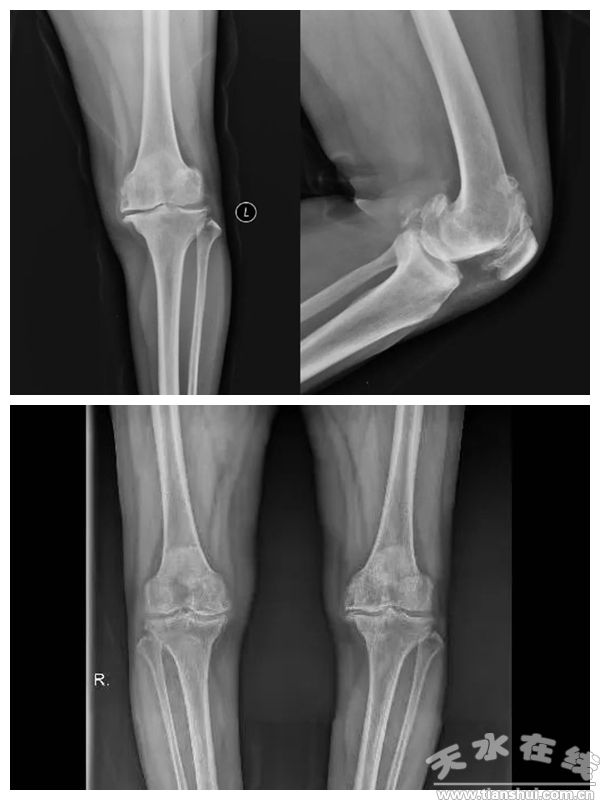

(患者術(shù)前X光線)

患者為56歲女性,左膝關(guān)節(jié)疼痛病史長達(dá)10余年,保守治療效果不佳,嚴(yán)重影響日常生活。經(jīng)診斷為“左膝關(guān)節(jié)骨性關(guān)節(jié)炎”,術(shù)前評估顯示膝關(guān)節(jié)嚴(yán)重退變,需行全膝關(guān)節(jié)置換術(shù)。與傳統(tǒng)手術(shù)相比,機(jī)器人輔助手術(shù)通過三維重建模型進(jìn)行精準(zhǔn)規(guī)劃,避免了髓內(nèi)定位操作,顯著提升了假體置入的精確度。